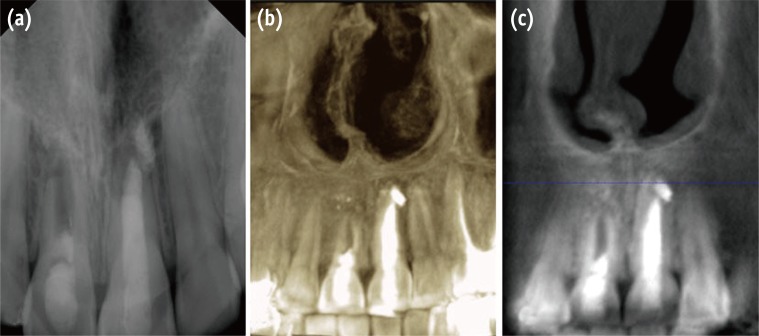

A 12 year old girl was referred from an orthodontic clinic to evaluate and treat the maxillary right central incisor (tooth #11). Her previous dental history was that the patient had trauma at age 9 years that affected her maxillary central incisors. She was referred by an orthodontist to a pedodontist in a private clinic to evaluate the traumatized teeth. An apexification was done for the maxillary left central incisor (tooth #21) using calcium hydroxide (Figure 1a) then she was referred back to her orthodontist who started the orthodontic treatment after one year. The patient developed buccal swelling one week after initiating the orthodontic treatment and the orthodontist sent the patient back to the pedodontist for the treatment on tooth #11. A regenerative endodontic retreatment was performed using MTA on tooth #11.

When this patient visited our clinic, she was an active orthodontic patient (Figure 1b). The tooth was asymptomatic and had a buccal sinus tract (Figure 1c). The medical history was unremarkable. Radiographic evaluation showed an immature open apex, with a large periradicular rarefaction and radiopaque material inside the root canal (Figure 1d). The intra-oral exam revealed an asymptomatic tooth #11 with an associated draining sinus tract. Clinical examination revealed no response to percussion and palpation tests. The tooth showed no mobility, and periodontal probing was within normal limits. The clinical diagnosis was previously treated asymptomatic periapical periodontitis.

Figure 1

(a) Diagnostic radiograph of the maxillary right central incisor (tooth #11) demonstrated incomplete root formation with diffuse periapical radiolucency and poor root canal filling; (b and c) Preoperative clinical photograph illustrates orthodontic treatment and the sinus tract related to tooth #11; (d) Periapical radiograph during orthodontic examination and before regenerative endodontic treatment that shows an open apex with apical rarefaction.

Figure 1 (a) Diagnostic radiograph of the maxillary right central incisor (tooth #11) demonstrated incomplete root formation with diffuse periapical radiolucency and poor root canal filling; (b and c) Preoperative clinical photograph illustrates orthodontic treatment and the sinus tract related to tooth #11; (d) Periapical radiograph during orthodontic examination and before regenerative endodontic treatment that shows an open apex with apical rarefaction.